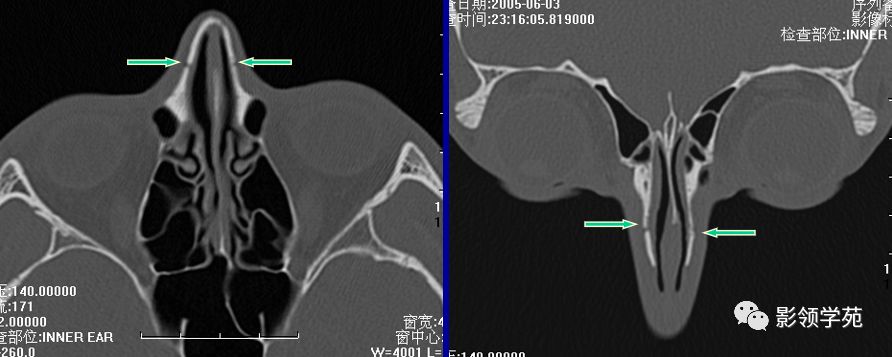

线性骨折 粉碎骨折

双侧鼻骨骨折

双侧上颌骨额突骨折

鼻中隔骨折